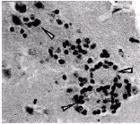

属节肢介体病毒中的披盖病毒(Togavirus)群,为风疹的病原病毒。由T.H.Weller与F.A.Neva(1962)及P.D.Parkman等(1962)自风疹患者的咽部洗涤液中分离到的。病毒粒子具多形性,50—85纳米,有包被。粒子中含有分子量为2.6—4.0×106的RNA(感染性核酸)。乙醚和0.1%的脱氧胆酸盐可使其钝化,在热中亦弱化。在兔或猪等动物的肾细胞中、或BSC-1、RK-13、BHK-21等细胞株中可增殖。由于这些细胞中一般不出现细胞变性(RK-13和BHK-21可以看到细胞变性),是否能够增殖,主要利用它干扰肠变胞病毒等的增值的性质来判断。通过患者鼻咽分泌物的飞沫直接传染,经14-21天潜伏期后,后头部、耳后部、颈部等处的淋巴节肿大,发热,并且1—2日后,颜面和头部即可出现风疹,并顺次扩大到颈部、躯干部和四肢,约经3日消退。如妊娠初期罹患风疹,胎儿常发生白内障、小眼球症、重听、心脏病和小头症等先天性异常。人是病毒唯一自然宿主.